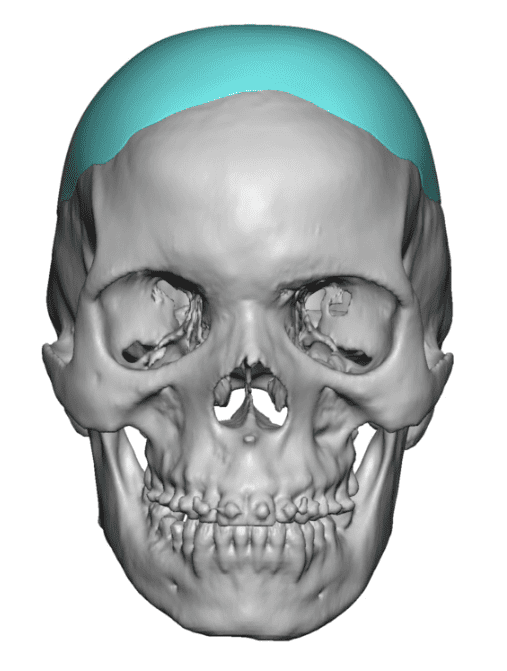

Desire for change of head shape from front view form an inverted V shape to a rounder and wider head shape.

Placement of custom extended forehead-temporal implants through incisions in the crease behind the ear. (he had a prior back of head skull implant which is green in the implant designs and which the head widening implants partially covered it)

Desire for change of head shape from front view form an inverted V shape to a rounder and wider head shape.

Placement of custom extended forehead-temporal implants through incisions in the crease behind the ear. (he had a prior back of head skull implant which is green in the implant designs and which the head widening implants partially covered it)